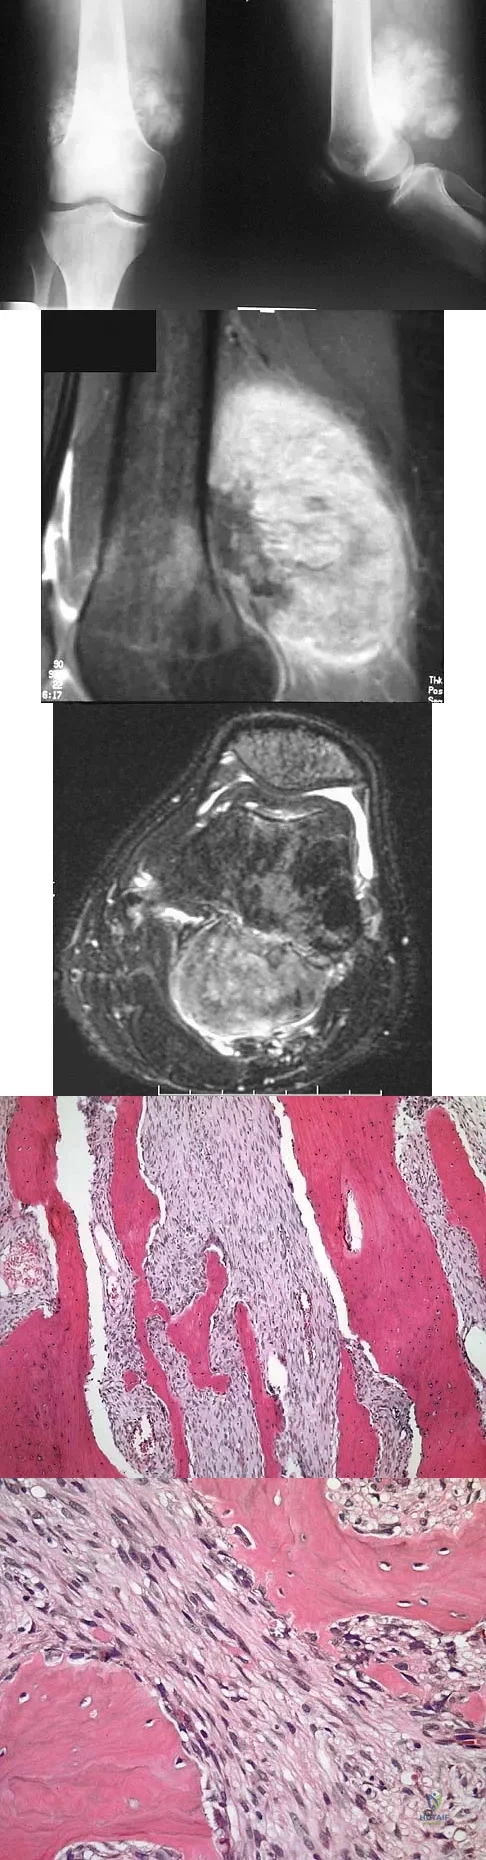

Question 35

A 16-year-old girl has a painful foot mass. A radiograph, MRI scan, and biopsy specimens are shown in Figures 35a through 35d. What is the most likely diagnosis?

Explanation